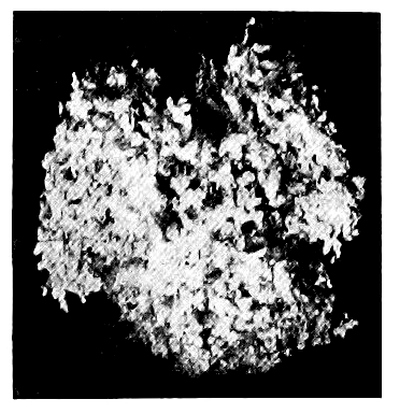

26. Photo-micrograph of Human Milk 177